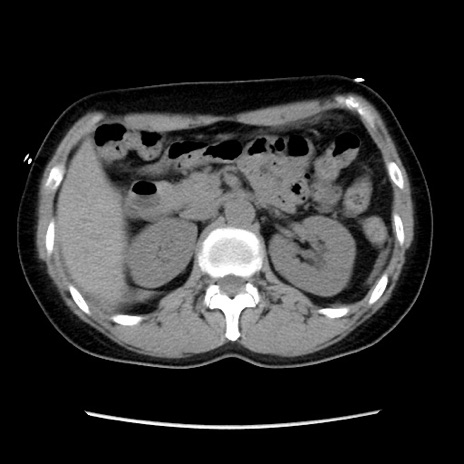

症例10(横断像)

【症例】 50歳代女性

【主訴】 腹痛

【現病歴】前日生レバーを食べた。今朝に排便あり。 昼前に突然発症の腹痛を生じ、当院救急外来を受診した。

【既往歴】 子宮筋腫にてで子宮全摘後

【身体所見】 意識清明、腹部:平坦、軟、下腹部やや左を中心に圧痛・反跳痛あり、筋性防御あり

【データ】WBC 7800、CRP 0.07